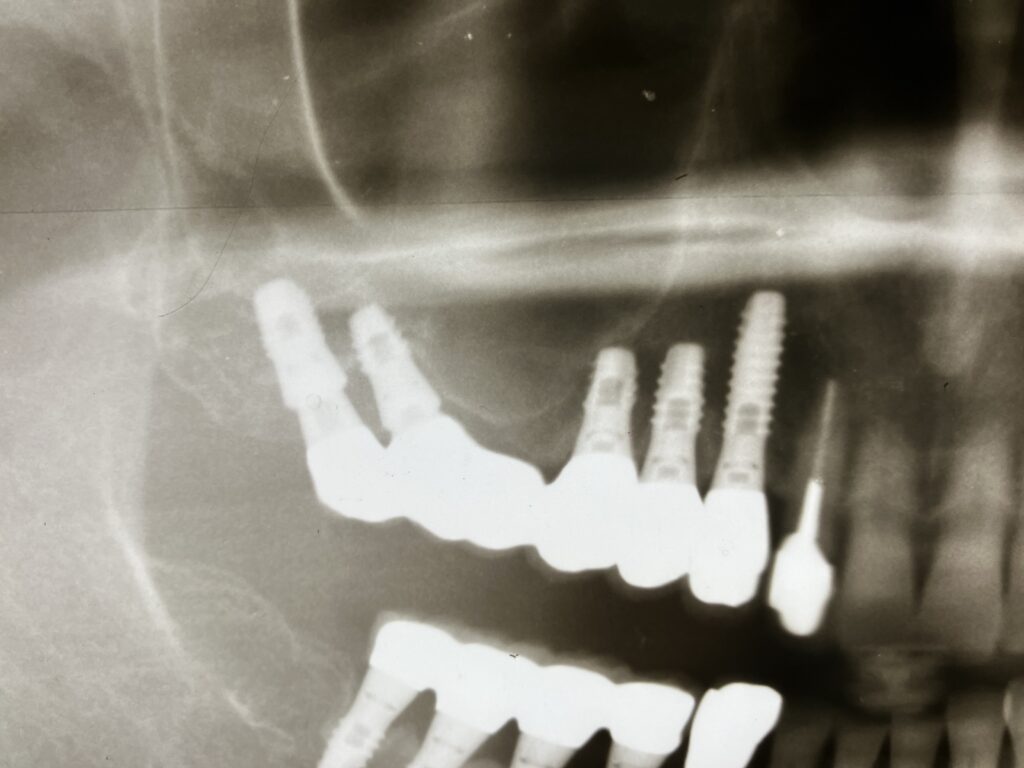

① 傾斜埋入(Tilted implant)

後方に向かって角度をつけて、上顎洞を避ける方法

いわゆる All-on-4 的な考え方

上顎洞前壁〜臼歯部皮質骨を狙う 長いインプラントが使える 即時荷重との相性が良い

④ 翼状突起インプラント(Pterygoid implant)

翼状突起 を利用

上顎洞を完全回避 非常に長いインプラント(15〜20mm) フルアーチ症例で有効

⑤ 頬骨インプラント(Zygomatic implant)

頬骨 に固定

重度骨吸収例で適応 サイナスリフト不要